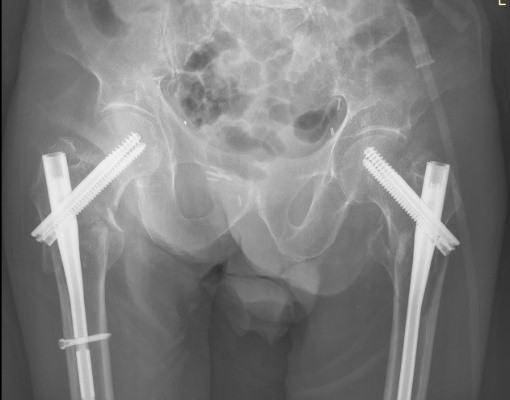

The patient was mobilized from the beginning with the help of our physiotherapists. The patient was discharged on the 7th post-operative day. Outpatient follow-up is satisfying. No surgical wound problems or infections were identified. At 6 weeks from surgery, radiographic evaluation was done (Fig. 4), and the patient was ambulatory with the help of crutches.

Figure 4: Six weeks post-operative X-ray.